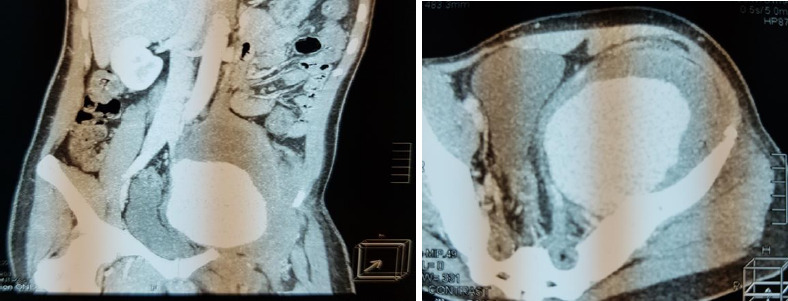

Isolated internal iliac artery aneurysm (IIIAA) is a rare condition, with limited information available about its symptoms and surgical treatment outcomes, particularly in Ghana. This case report presents the 4-year surgical treatment outcomes of three patients (aged 42, 58, and 22 years) with IIIAA, each exhibiting different clinical presentations. All patients experienced pelvic pain and difficulty walking but had uneventful post-operative recoveries. They made significant progress with physiotherapy and were able to mobilise with a Zimmer frame before discharge. Currently, all three patients are mobilising unaided, and post-operative Computed Tomography (CT) scans show no complications. This report highlights the importance of early diagnosis to minimise complications and improve the prognosis for IIIAA, which often presents asymptomatically and can manifest with a wide range of clinical findings. The study underscores the effectiveness of open surgical repair in achieving positive outcomes for IIIAA patients in Ghana.